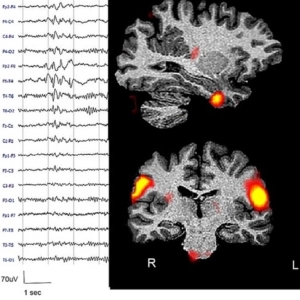

Tutor: Prof. Anna Elisabetta Vaudano – Phenotypic characterization of late-onset epilepsies (LOE) through serum biomarkers, cognitive testing and advanced brain imaging techniques

Tutor: Prof. Anna Elisabetta Vaudano – Neuro-vascular coupling patterns during wakefulness and sleep in Genetic Generalized Epilepsies (GGE)